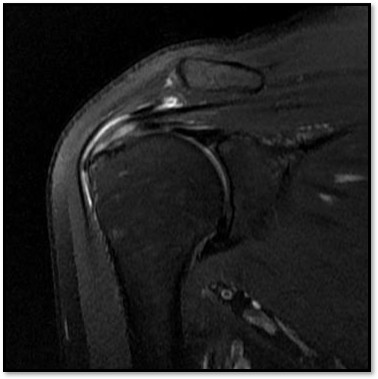

MRI와 초음파를 다시 검토했습니다.

회전근개 극상건의 관절면측(articular-side) 부분파열.